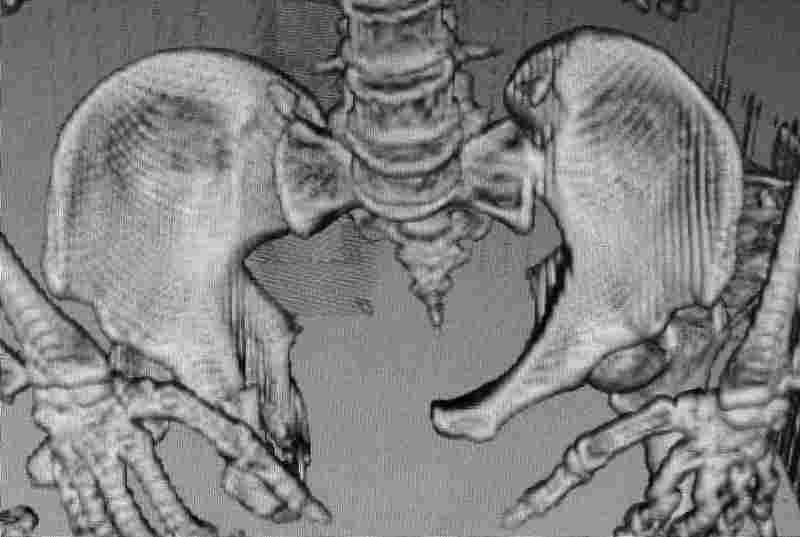

Молодой парень, без соматики. Сейчас чуть больше 2-х нед после операции, швы сняты, мочится сам. Был тяжелый, после операции дней 10 пытался выполнить лежа поперечный шпагат (успешно, так и лежал большей частью, может быть из-за обширной гематомы промежности). Репозиция не идеальная, но фиксация довольно надежная, за 2 нед ничего не "разъехалось". Сейчас пришел в ум. Когда по-вашему можно дать нагрузку и на какую ногу или на обе? Или вообще подскажете программу реабилитации.PS Заранее извиняюсь за качество снимков, до не делали (body scan), если не видно - то - полные разрывы КПС с двух сторон. после КТ сломался. Неврологии вроде бы нет.